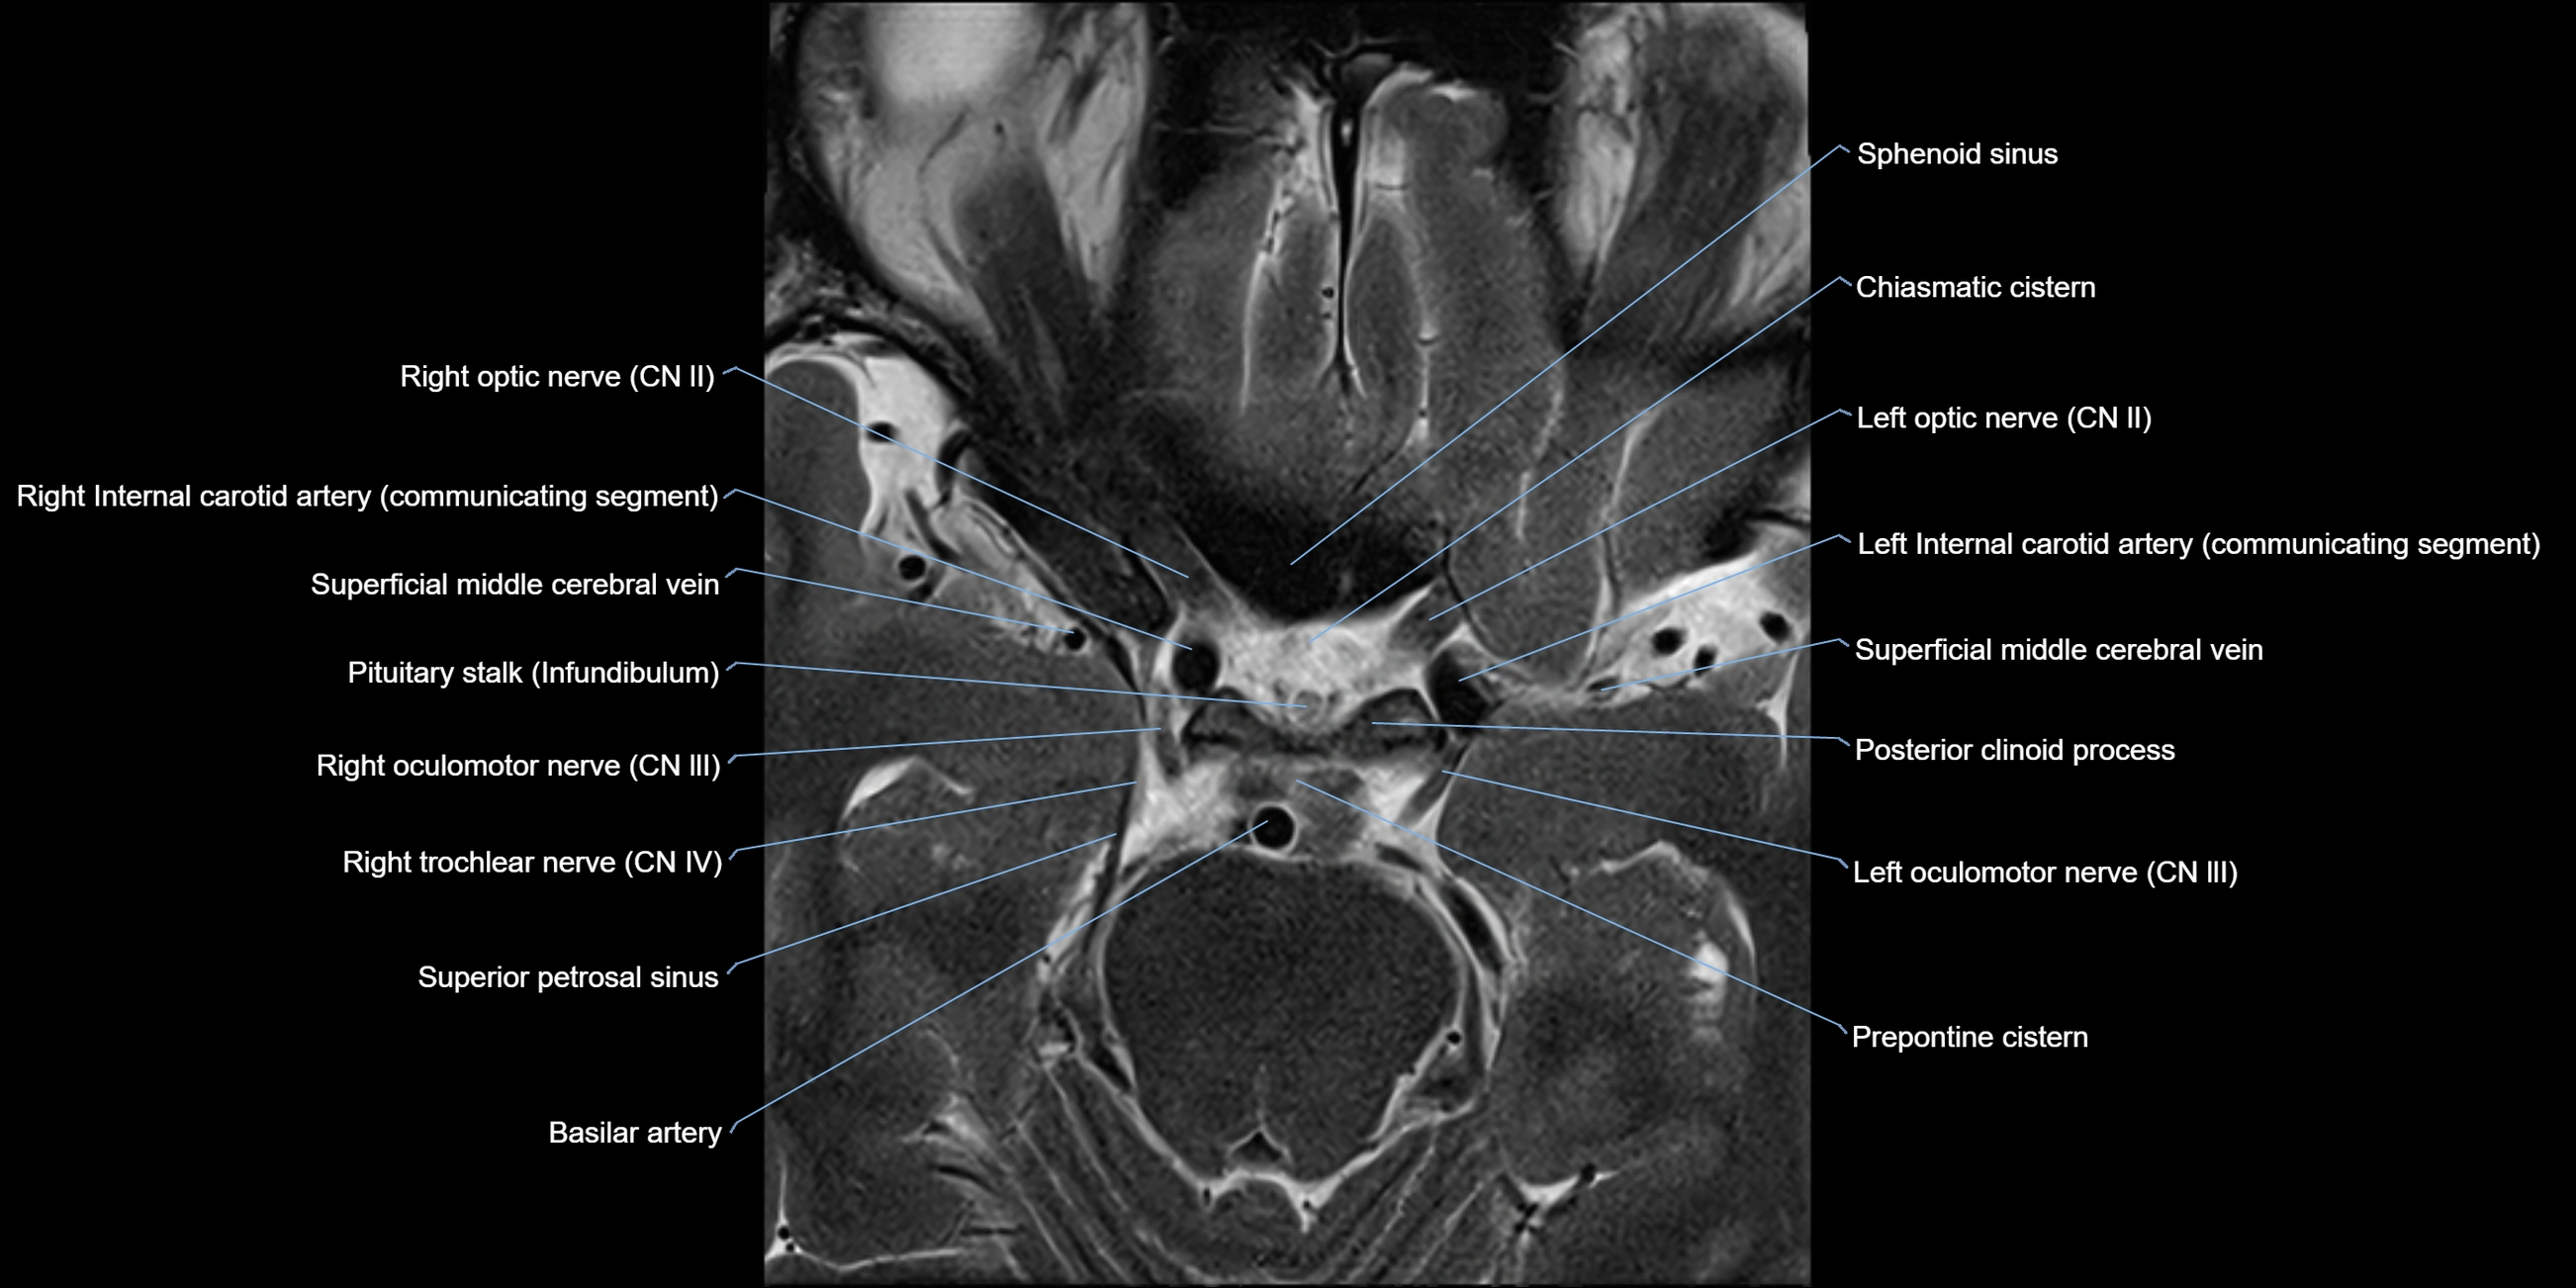

MRI images